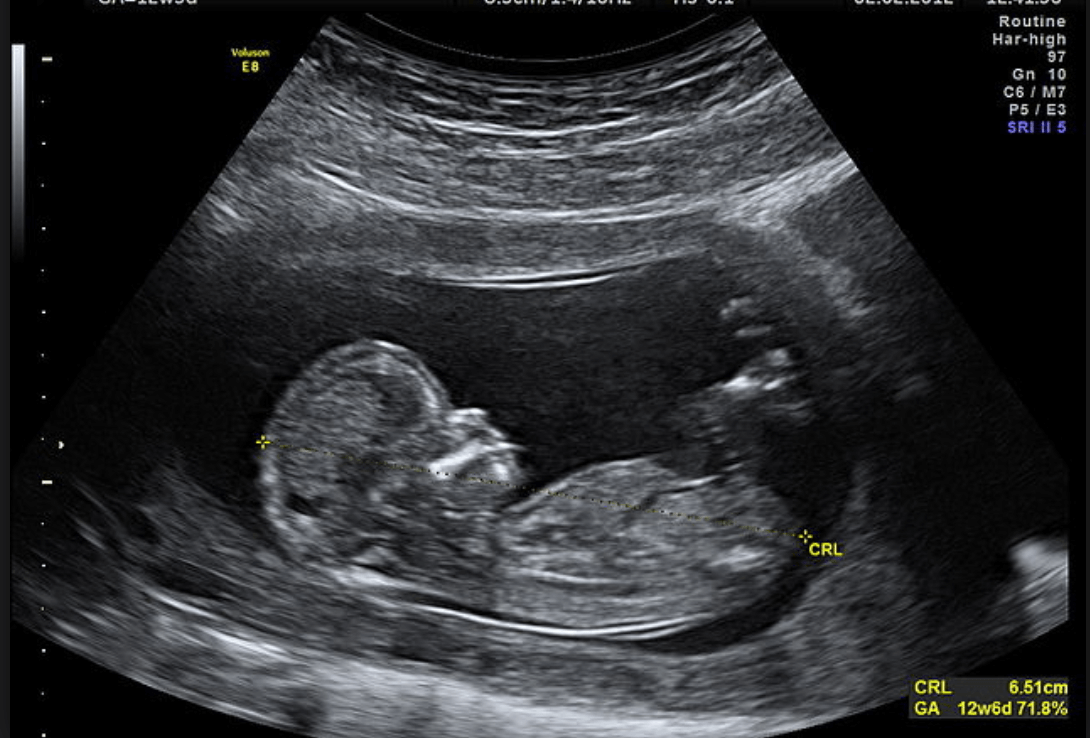

Diese Ultraschalluntersuchung wird durchgeführt, um festzustellen, ob sich die Schwangerschaft weiter entwickeln kann. Der Arzt/die Ärztin prüft, ob der Embryo lebt, ob eine Fruchtblase vorhanden ist und wie viele Embryonen vorhanden sind. Außerdem wird die Größe des Fötus gemessen, vom Schädel bis zum Steißbein, um das Schwangerschaftsalter zu bestimmen.